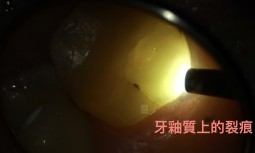

牙齒咬起來怪怪的,有點不舒服------牙齒裂痕,造成牙髓壞死,顯微根管與全瓷嵌體修復 -